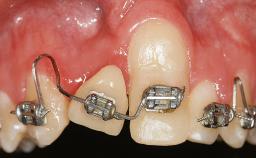

In 1983, a 51-year-old non-smoking patient was referred for the treatment of moderate chronic periodontitis. At the initial examination, 47% of sites exhibited probing depths of 4 to 6 mm. Periodontal therapy consisted of initial periodontal treatment including oral-hygiene instructions and supra- and subgingival debridement, followed by periodontal surgery to eliminate residual pockets.

| Periodontal Status | History of periodontitis or genetic predisposition |